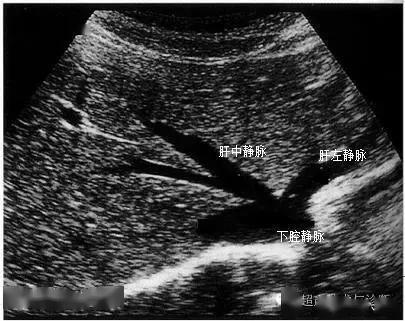

超声肝的分段解剖图片,肝超声分段解剖示意图

肝脏的分叶分段(解剖 超声声像图)

肝脏超声分段

肝静脉解剖